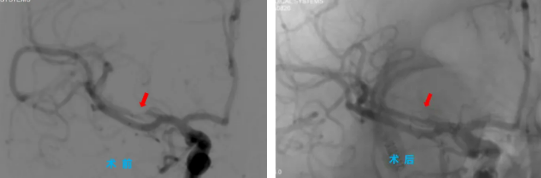

手術當天,院長助理、神經(jīng)內(nèi)科主任程偉與神經(jīng)內(nèi)科三病區(qū)副主任彭偉聯(lián)手為患者主刀,通過高難度的微創(chuàng)介入治療,成功為患者大腦中堵塞的血管進行了球囊擴張并置入支架,打通了“生命通道”。術后,患者手腳能活動了,說話也清楚了,恢復得一天比一天好,一周后,患者康復出院。